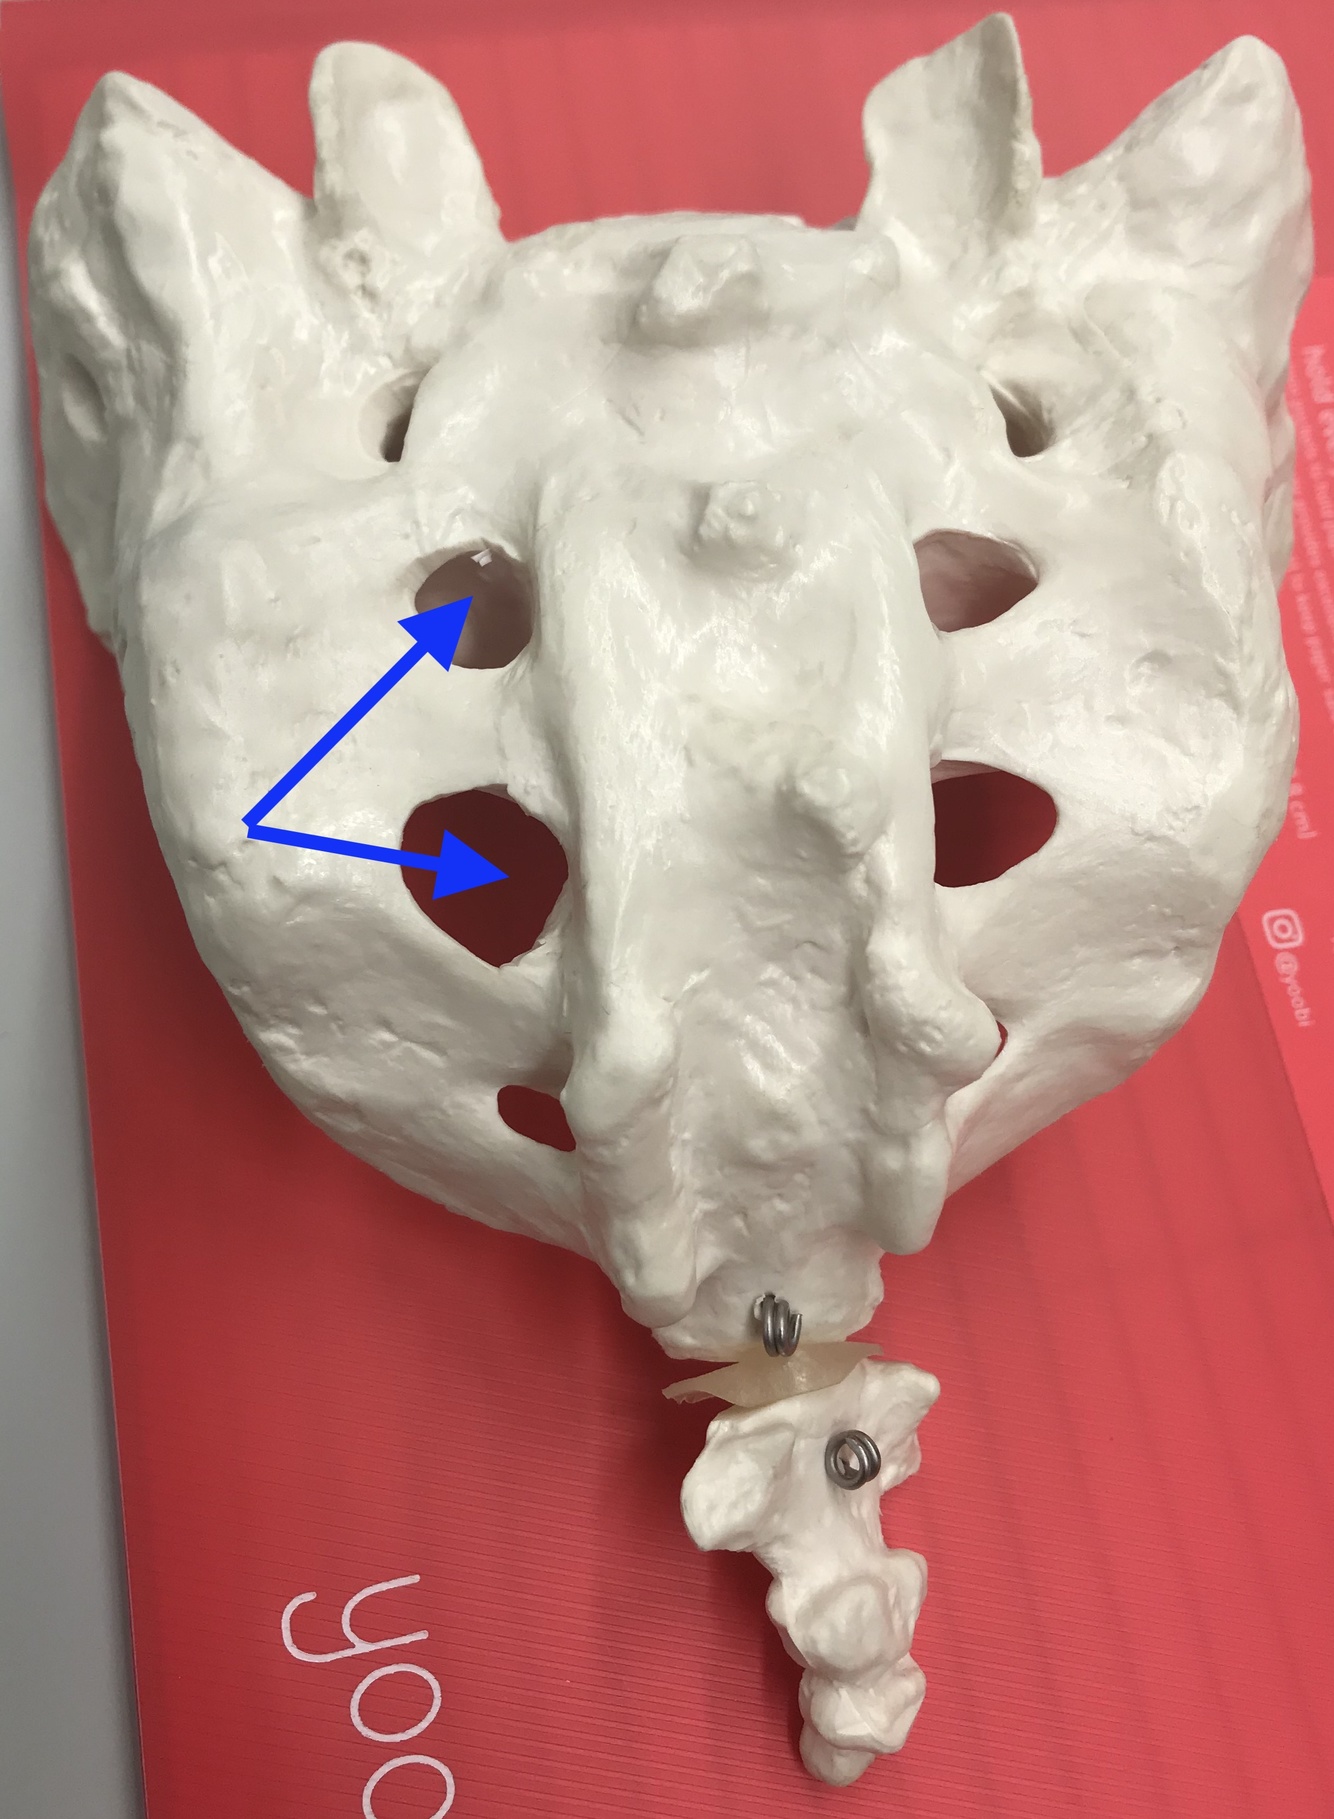

dorsal sacral foramina

ventral sacral foramina

lateral crest